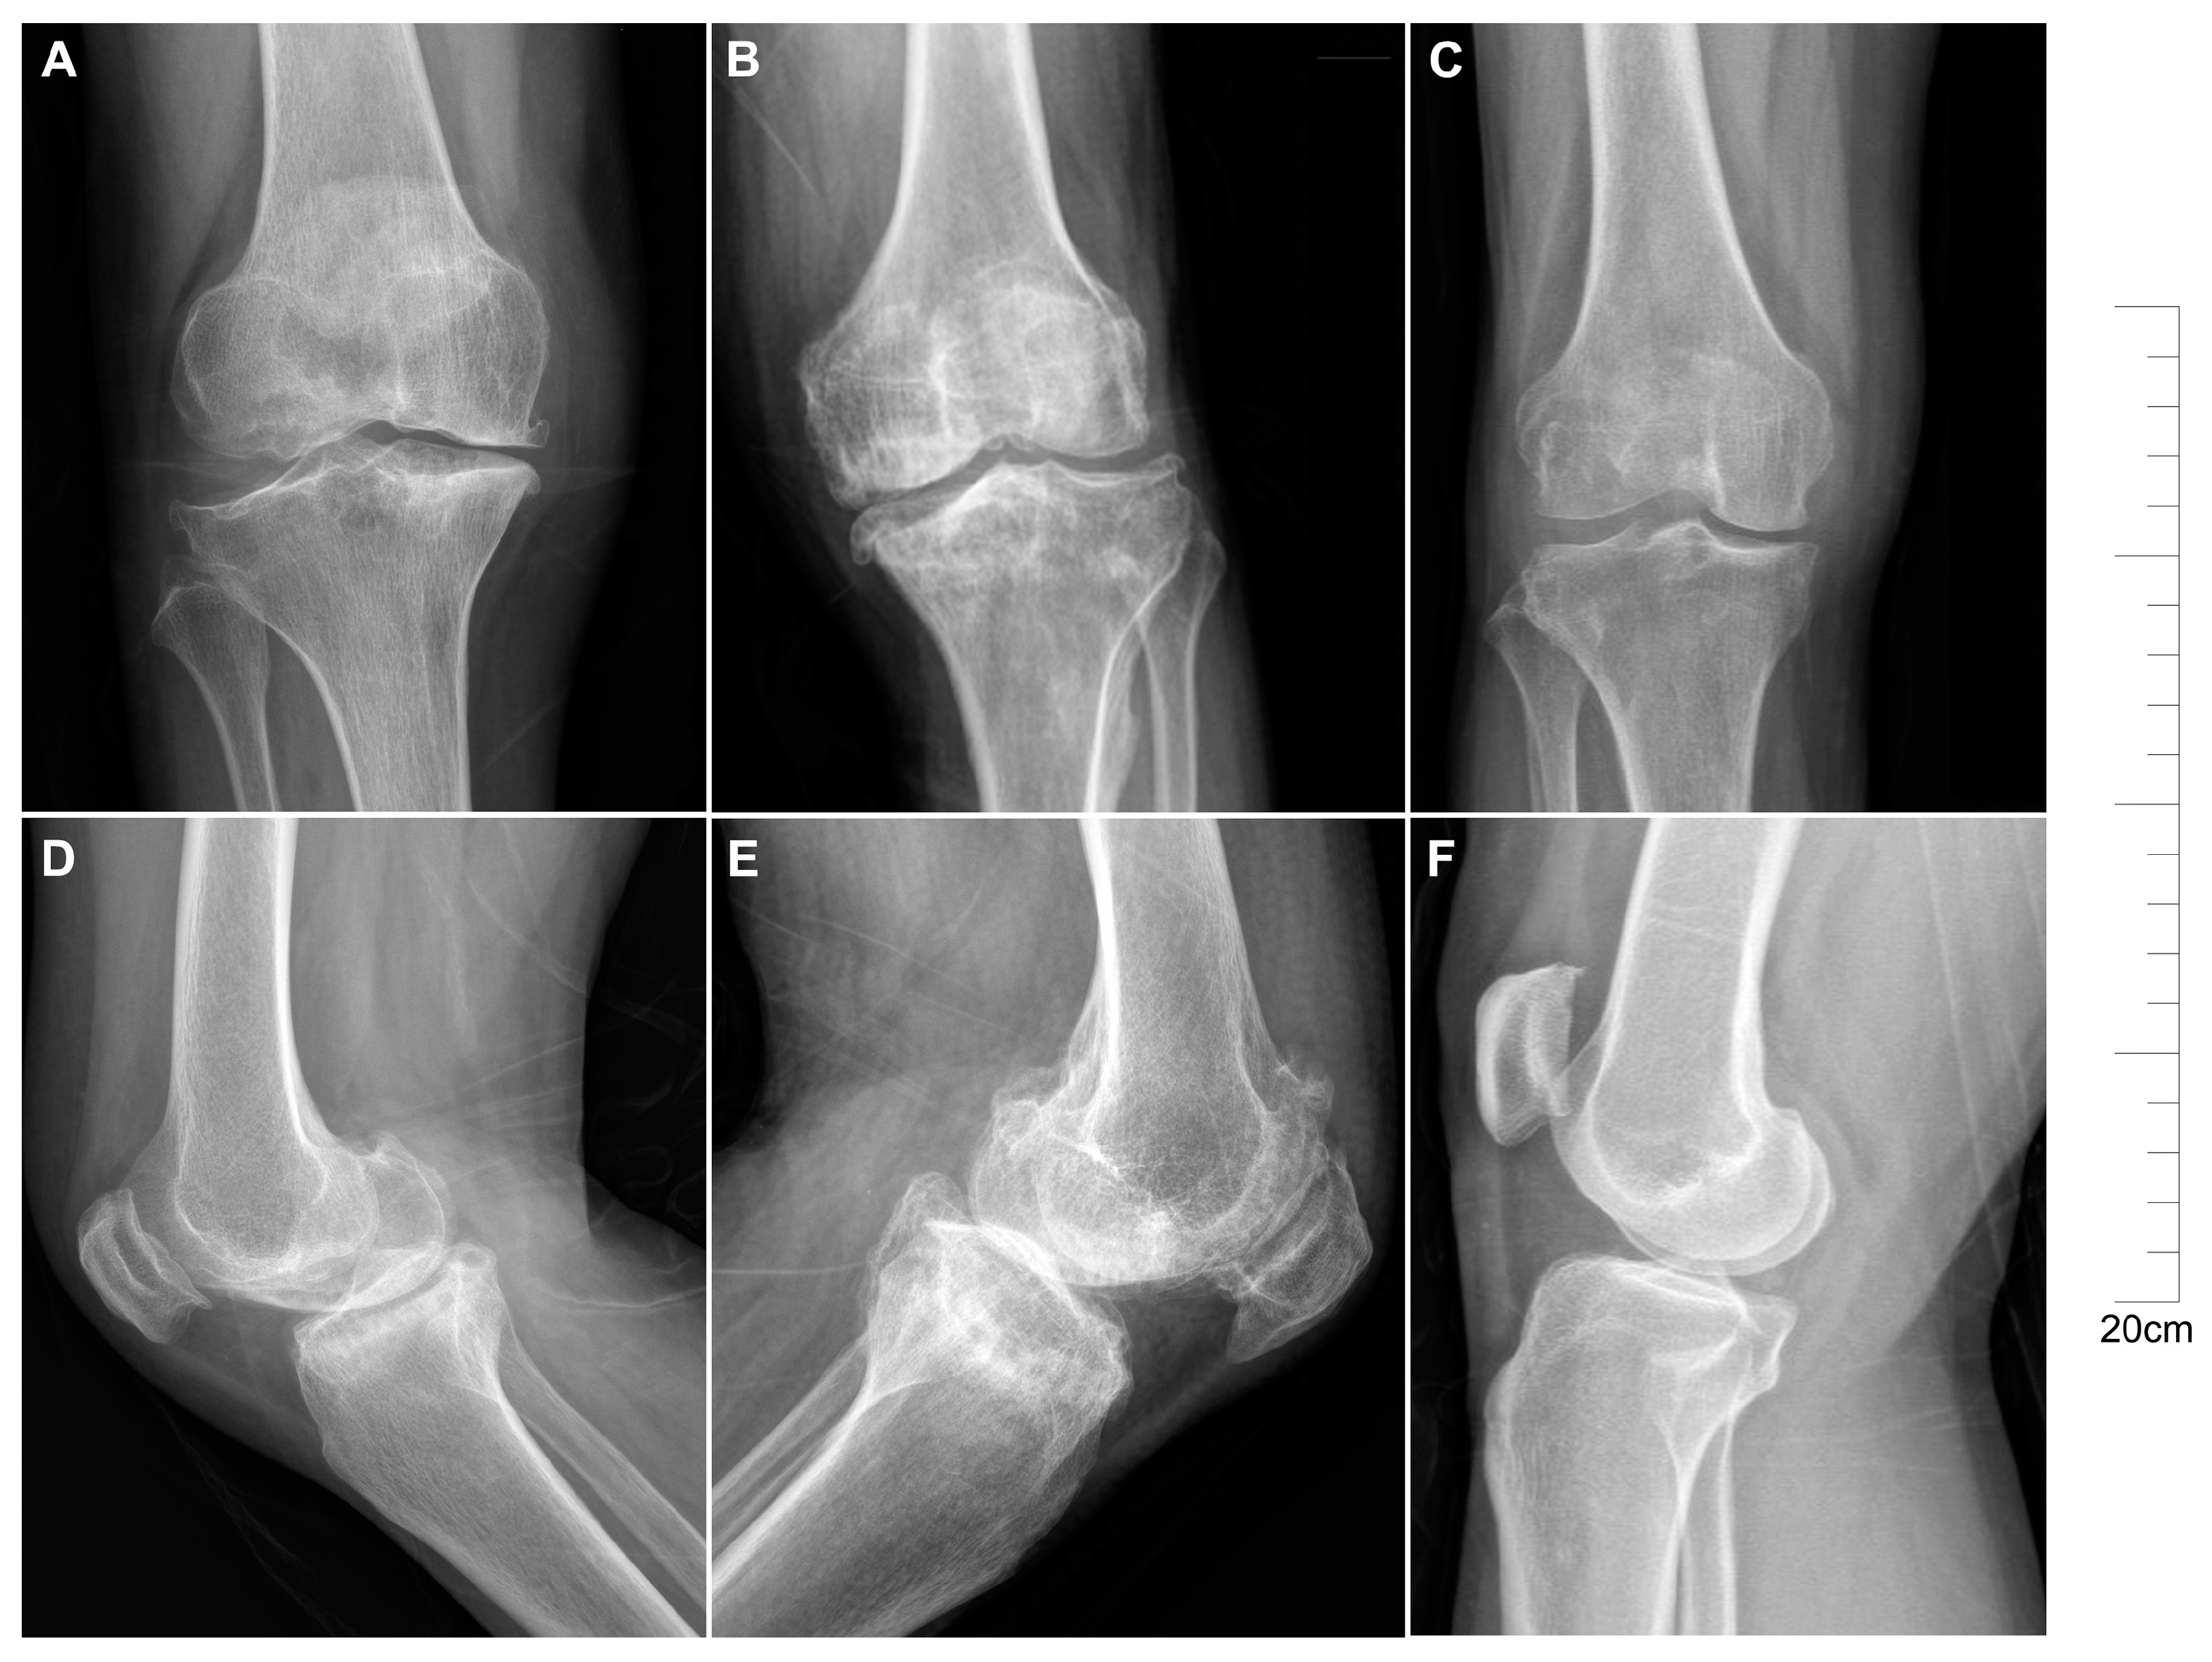

2.1. Descriptive Characteristics of Patients with KBD and OA